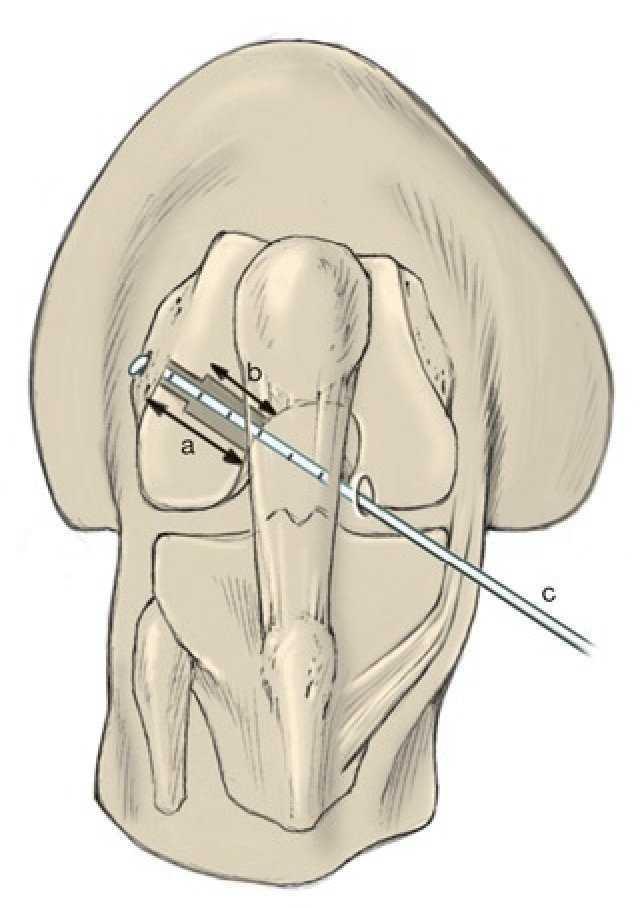

Fig. 2 Para la cirugía de reemplazo artroscópica del ligamento cruzado anterior son necesarios dos abordajes artroscópicos hacia la articulación de la rodilla. La extracción del tendón se realiza a través de una incisión oblicua de 3 cm de longitud aproximadamente, medial a la tuberosidad tibial (fig. 5). A través de este abordaje se realiza también la perforación del túnel tibial. El artroscopio se introduce a través de un portal anterolateral alto (A). El portal anterolateral alto ofrece un buen ángulo de visión sin que los cuerpos adiposos infrapatelares puedan desplazarse por delante del artroscopio. A través del portal medial (B) se realiza la preparación de la inserción femoral del LCA y se perfora también el túnel femoral. A través de un portal anteromedial alto (C) el proceso de perforación se puede controlar mediante artroscopia. Otras intervenciones adicionales en el menisco se pueden realizar a través del portal medial. En caso de que la accesibilidad del menisco sea difícil a través de este portal, serán necesarios otros abordajes (línea).

Fig. 8 La guía y la broca para la realización del túnel femoral pueden insertarse ya sea a través del túnel tibial (transtibial) o del portal medial. El inconveniente de la técnica transtibial es que la inserción femoral del ligamento cruzado anterior solo se puede alcanzar cuando el túnel tibial se encuentra ubicado mucho más medial (a). La guía y la broca tienen más libertad de movimiento cuando se introducen a través del portal medial (b).

Fig. 9 a) La guía para la colocación del alambre guía para la broca se introduce en la articulación a través del portal medial. En la técnica de perforación de portal se deben utilizar guías diseñadas especialmente para esta técnica (por ejemplo, MPA, Karl Storz, Tuttlingen). Para colocar el alambre guía la rodilla tiene que estar flexionada en más de 110º. b) El gancho doblado de la guía se apoya por detrás de la línea intercondílea en la fascia poplítea. Se pueden elegir varias distancias entre gancho y guía.

Fig. 10 a) El gancho de la guía se desplaza por detrás de la línea inter-condílea. b) A continuación se perfora el alambre guía (2,4 mm) en el centro de la inserción del ligamento cruzado anterior.